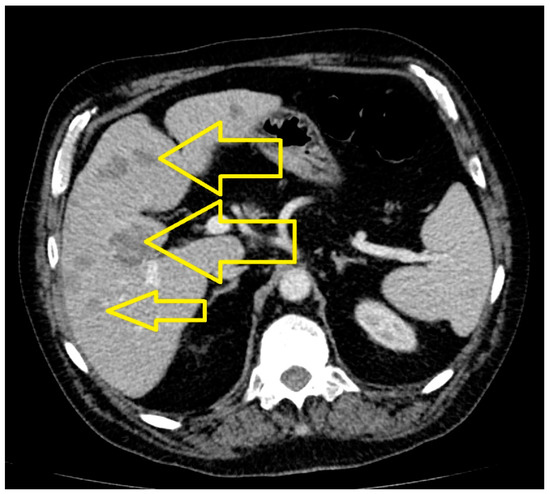

2. Case Presentation